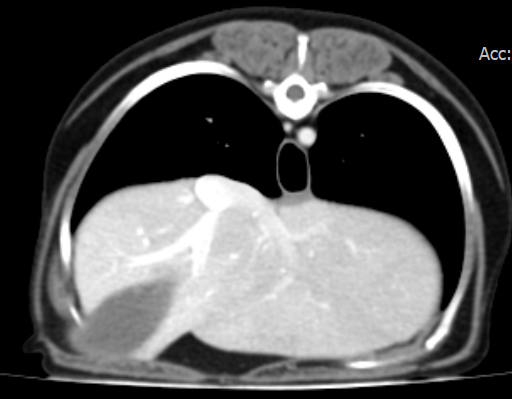

신체검사 및 영상검사 결과, 우측 5번 유선에 종양이 확인되었고, 3~5번 유선이 서로 연결되어 있어 부분 절제 시 재발 위험이 높았습니다. 이에 따라 우측 3~5번 유선 절제술을 계획하였고, 본원 영상진단센터에서 전이 평가를 위해 전신 CT를 촬영하였습니다.

유선종양 CT 결과 / 출처: 24시 온숲동물의료센터

CT 결과, 폐·복부 장기 등 타 장기로의 전이는 확인되지 않았습니다.

이는 유선종양이 국소 부위에 국한된 상태로, 수술을 통한 완전 절제가 가능하다는 판단을 내릴 수 있었습니다.

온숲동물의료센터는 병원 내 자체 CT 장비를 보유하고 있어 유선종양 환자의 전이 평가부터 수술 후 CT 추적관리까지 원스톱으로 진행할 수 있습니다.